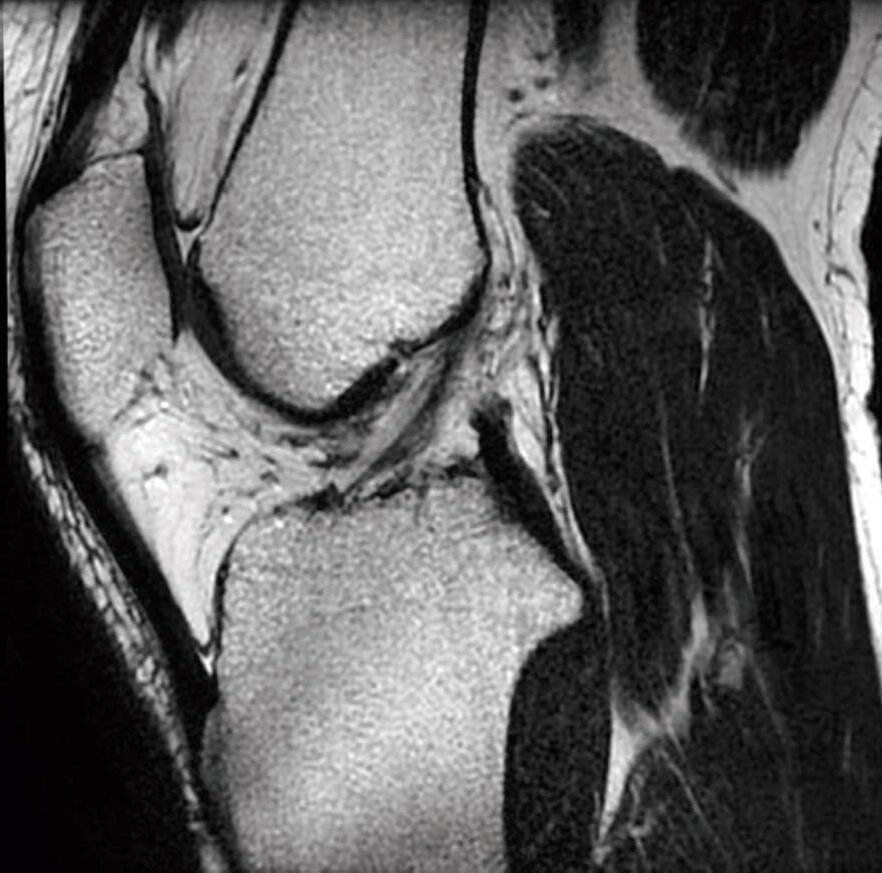

膝関節MR像(別冊No.2)を別に示す。正しい組合せはどれか。

- 1ア

腓腹筋

- 2イ

外側広筋

- 3ウ

内側半月板

- 4エ

前十字靱帯

- 5オ

膝蓋靱帯